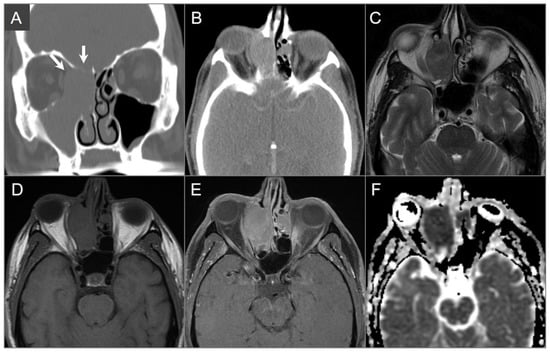

4.4.4. Endolymphatic Sac Tumor